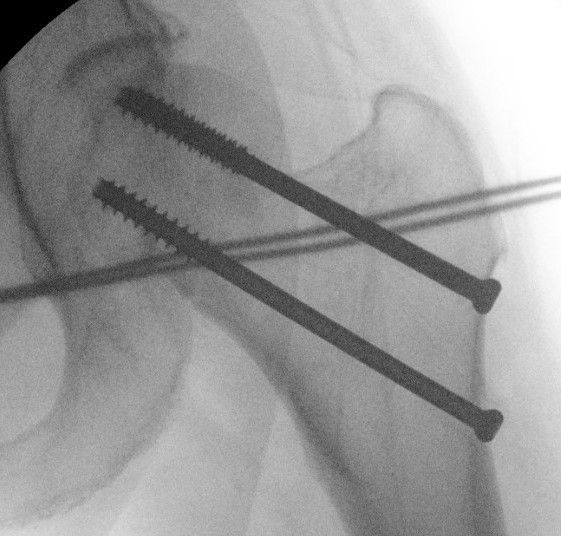

Cannulated screws

Technique

Lateral on traction table

- adequate reduction / no varus

- small incision or percutaneous

- 3 screws

- ensure inferior screw entry point is above lesser trochanter to prevent fracture

- ensure threads cross fracture site entirely to obtain compression

- need correct screw length so screw head can compress against cortex